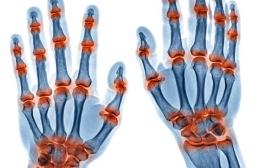

J ai Mal Bras et mains Bras et mains Tête et cou Torse et haut du dos Jambes et pied